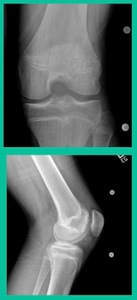

Another case example. 14-year-old male tennis player, 10 months of knee pain (Figure 7A).

This is a Trochlear defect (Figure 7B).

This goes back to metallic screw fixation, because this one is macroscopically unstable. That is a fracture non-union. That’s an atrophic non-union. Debride it, curette it, drill it, and thenwe use metal screws because it’s macroscopically unstable.

However, in this instance, we did take the screws out.

He was back to everything at 16 weeks and, at two years, he had no further symptoms. How do these do? There’s plenty of literature that shows that metallic screw fixation for unstable OCD, not just in juveniles, but in adults, will lead to reliable fixation. It’s a four-month process. They get back to everything, and they rarely have problems downstream.